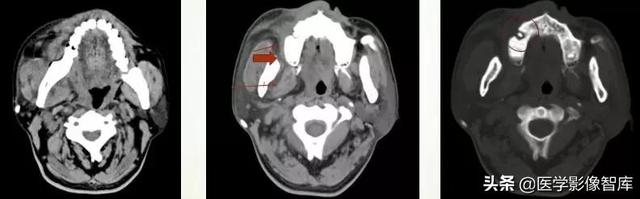

咀嚼肌间隙、翼下颌间隙、颊间隙

男,31岁,患者约3天前出现右侧面部口角区局限性肿胀,无明显触压痛,既往右侧下颌后牙区阵发性锐痛,曾自行口服消炎药处理,自诉牙痛症状无明显缓解,约3天前牙痛症状加重,伴夜间痛,后自觉右侧面部肿胀,约2天前开始发热,体温39.8℃。